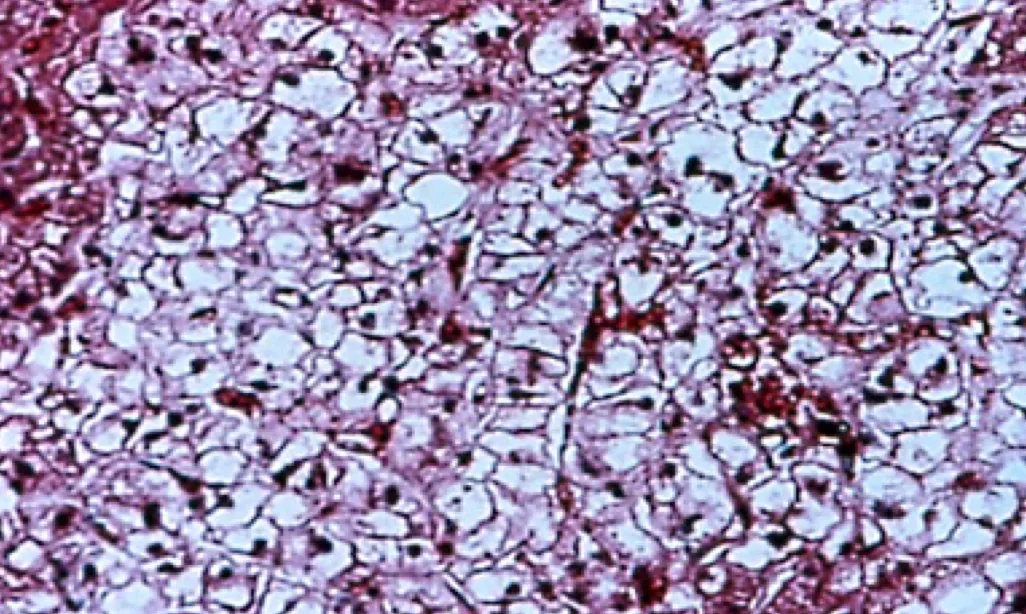

Hepatic biopsy: Identify primary hepatic disease, such as lipidosis, neoplasia, vascular, or inflammatory/fibrotic disease. Steroid hepatopathy is characterized by the presence of vacuoles in hepatocytes, which most studies suggest are filled with glycogen5 (Figure 1). May be associated with endogenous or exogenous administration of corticosteroids or with endogenous excess of other adrenal steroids, such as 17-hydroprogesterone.10

Steroid hepatopathy in a dog on immune-suppressive doses of prednisone